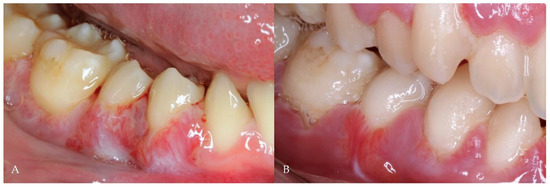

2.1. Case Report